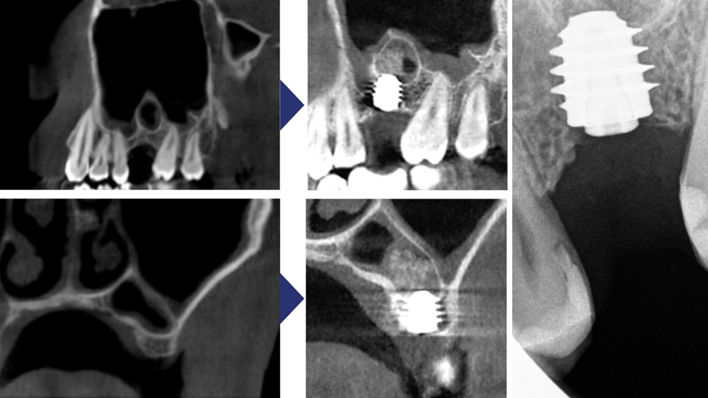

Clinical case: Delayed implant placement: sinus floor elevation by means of lateral

approach & implant placement with GBR

- Courtesy of Dr. Irfan Abas, Netherlands -

Clinical case: Installation of dental implants in complicated anatomic conditions using crest lifting methods

- Courtesy of Dr.Alexander Lysov, Russia -

AnyRidge, complicated anatomic conditions, crest lift, MICA Kit, Dr. Alexander Lysov, bone regeneration, GBR, #26, maxillary posterior

AnyRidge implant system, MICA Kit